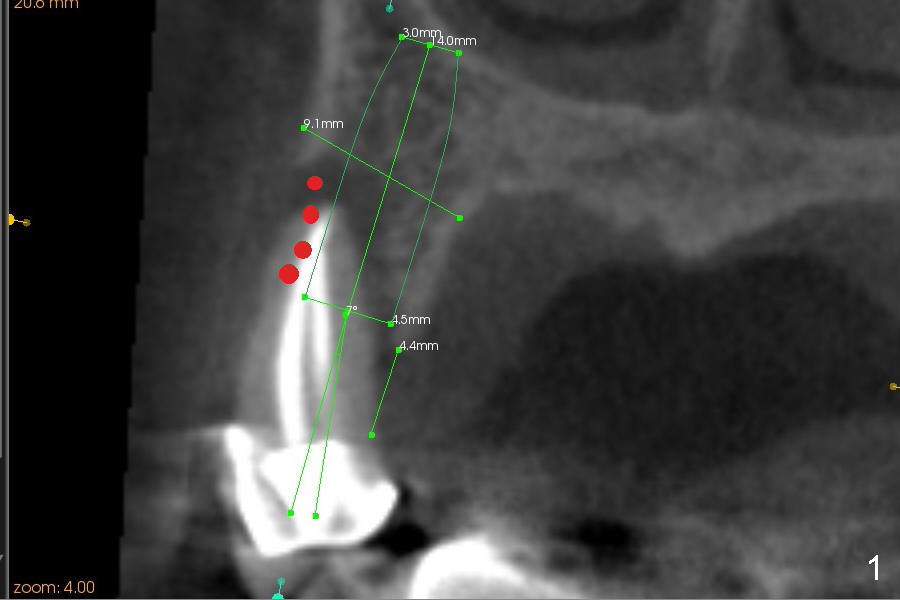

The radiolucency is more or less confined to the apical region. The fistula is most likely due to endo failure. The buccal and lingual canals fuse before exit. Debridement and filling were not done properly. Although root canal retreatment is an option, implant replacement offers long term prognosis.

It appears that there is a buccal bony defect coronally. The implant is placed more or less palatally (in position and tilt) for better restoration. Either bone level (4.5x14 mm, Fig.1) or tissue-level (4.5x20, Fig.2) implant is placed. The diameter is more or less determined by the adjacent teeth (Fig.3). A 4.5x14 mm bone level implant should obtain sufficient primary stability (Fig.4). If not, either the diameter or length of the implant is to be increased.